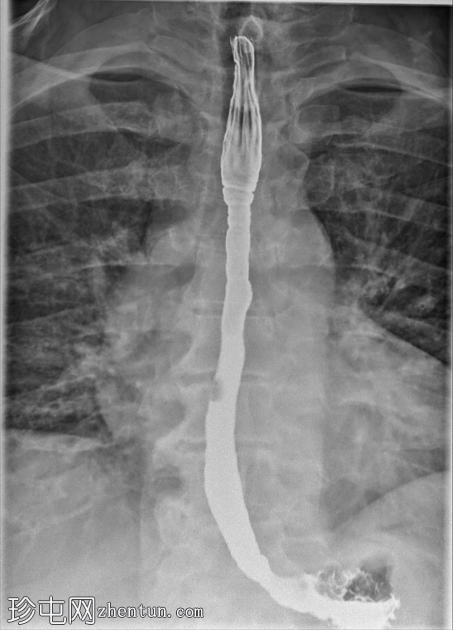

透视食管造影显示食管内可见同心环状轻度狭窄,符合嗜酸性食管炎的影像学表现。近端食管轻度扩张,提示存在固定性狭窄。未见肿块或食管裂孔疝。

钡餐食管造影通常显示固定的同心环(“气管化”)、节段性狭窄或食管管径变细。